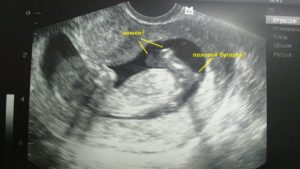

Но на ультразвуковом исследовании 15-й недели уже можно увидеть работу дыхательной системы. Плод активно заглатывает, а затем выплевывает амниотическую жидкость.

На экране же малыш выглядит длиною около пальца. Если выполняют 3D УЗИ, то на экране видно недовольство крохи, которое проявляется при нажатии на живот датчиком. Ребенок может хмурить бровки, хвататься за пуповину, активнее двигаться.

Кольца пуповины или ручки ребенка иногда воспринимаются как пенис мальчика, и потому могут возникать ошибки в определении пола крохи, которые при следующем УЗИ исправляются.